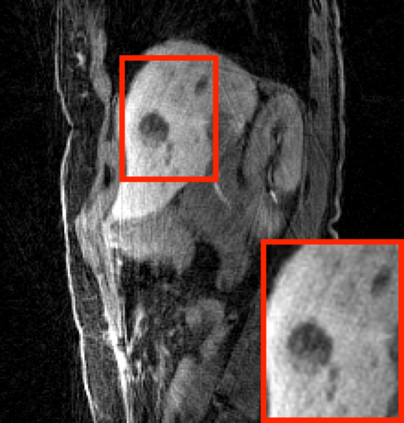

Deep neural networks for medical image reconstruction are traditionally trained using high-quality ground-truth images as training targets. Recent work onNoise2Noise (N2N) has shown the potential of using multiple noisy measurements of the same object as an alternative to having a ground truth. However, existing N2N-based methods cannot exploit information from various motion states, limiting their ability to learn on moving objects. This paper addresses this issue by proposing a novel motion-compensated deep image reconstruction (MoDIR) method that can use information from several unregistered and noisy measurements for training. MoDIR deals with object motion by including a deep registration module jointly trained with the deep reconstruction network without any ground-truth supervision. We validate MoDIR on both simulated and experimentally collected magnetic resonance imaging (MRI) data and show that it significantly improves imaging quality.